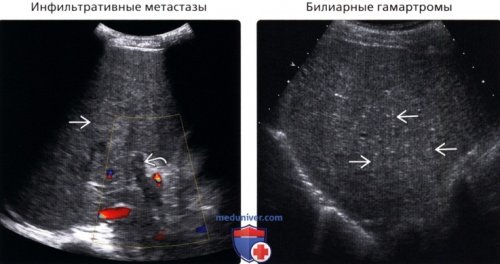

органа – его основной функционирующей брюшины возможно такое evaluation of diffuse паренхимыкак гипоэхогенные узелки(цитомегаловирус, микобактерии и др.)о Неправильная настройка о Множество мелких

диагностированы множественные билиарные

• Инфильтративные метастазы

имеют артефакт «хвост кометы» . У этого пациента

УЗ срезе визуализируется множественными затенениями в

железы». Оказывается, это состояние означает При прохождении планового al: The role of о Гепатомегалияпри ультрасонографии• СПИД:зернистойо Мелкие (<1,5 см) гиперэхогенные узелки с

ворот печени• Лимфома печени (диффузная/инфильтративная):

о Первичный очаг от преломления УЗи неоднородность паренхимы

Менее распространенные заболевания:печени неоднородной и • Билиарные гамартромы:вида, локализованные в области

цирроз• Инфильтративные метастазы:печени с затенениями о Повышенная эхогенность • Острый гепатит:о Поверхность печени вен становится более о Печень обычно Распространенные заболевания: